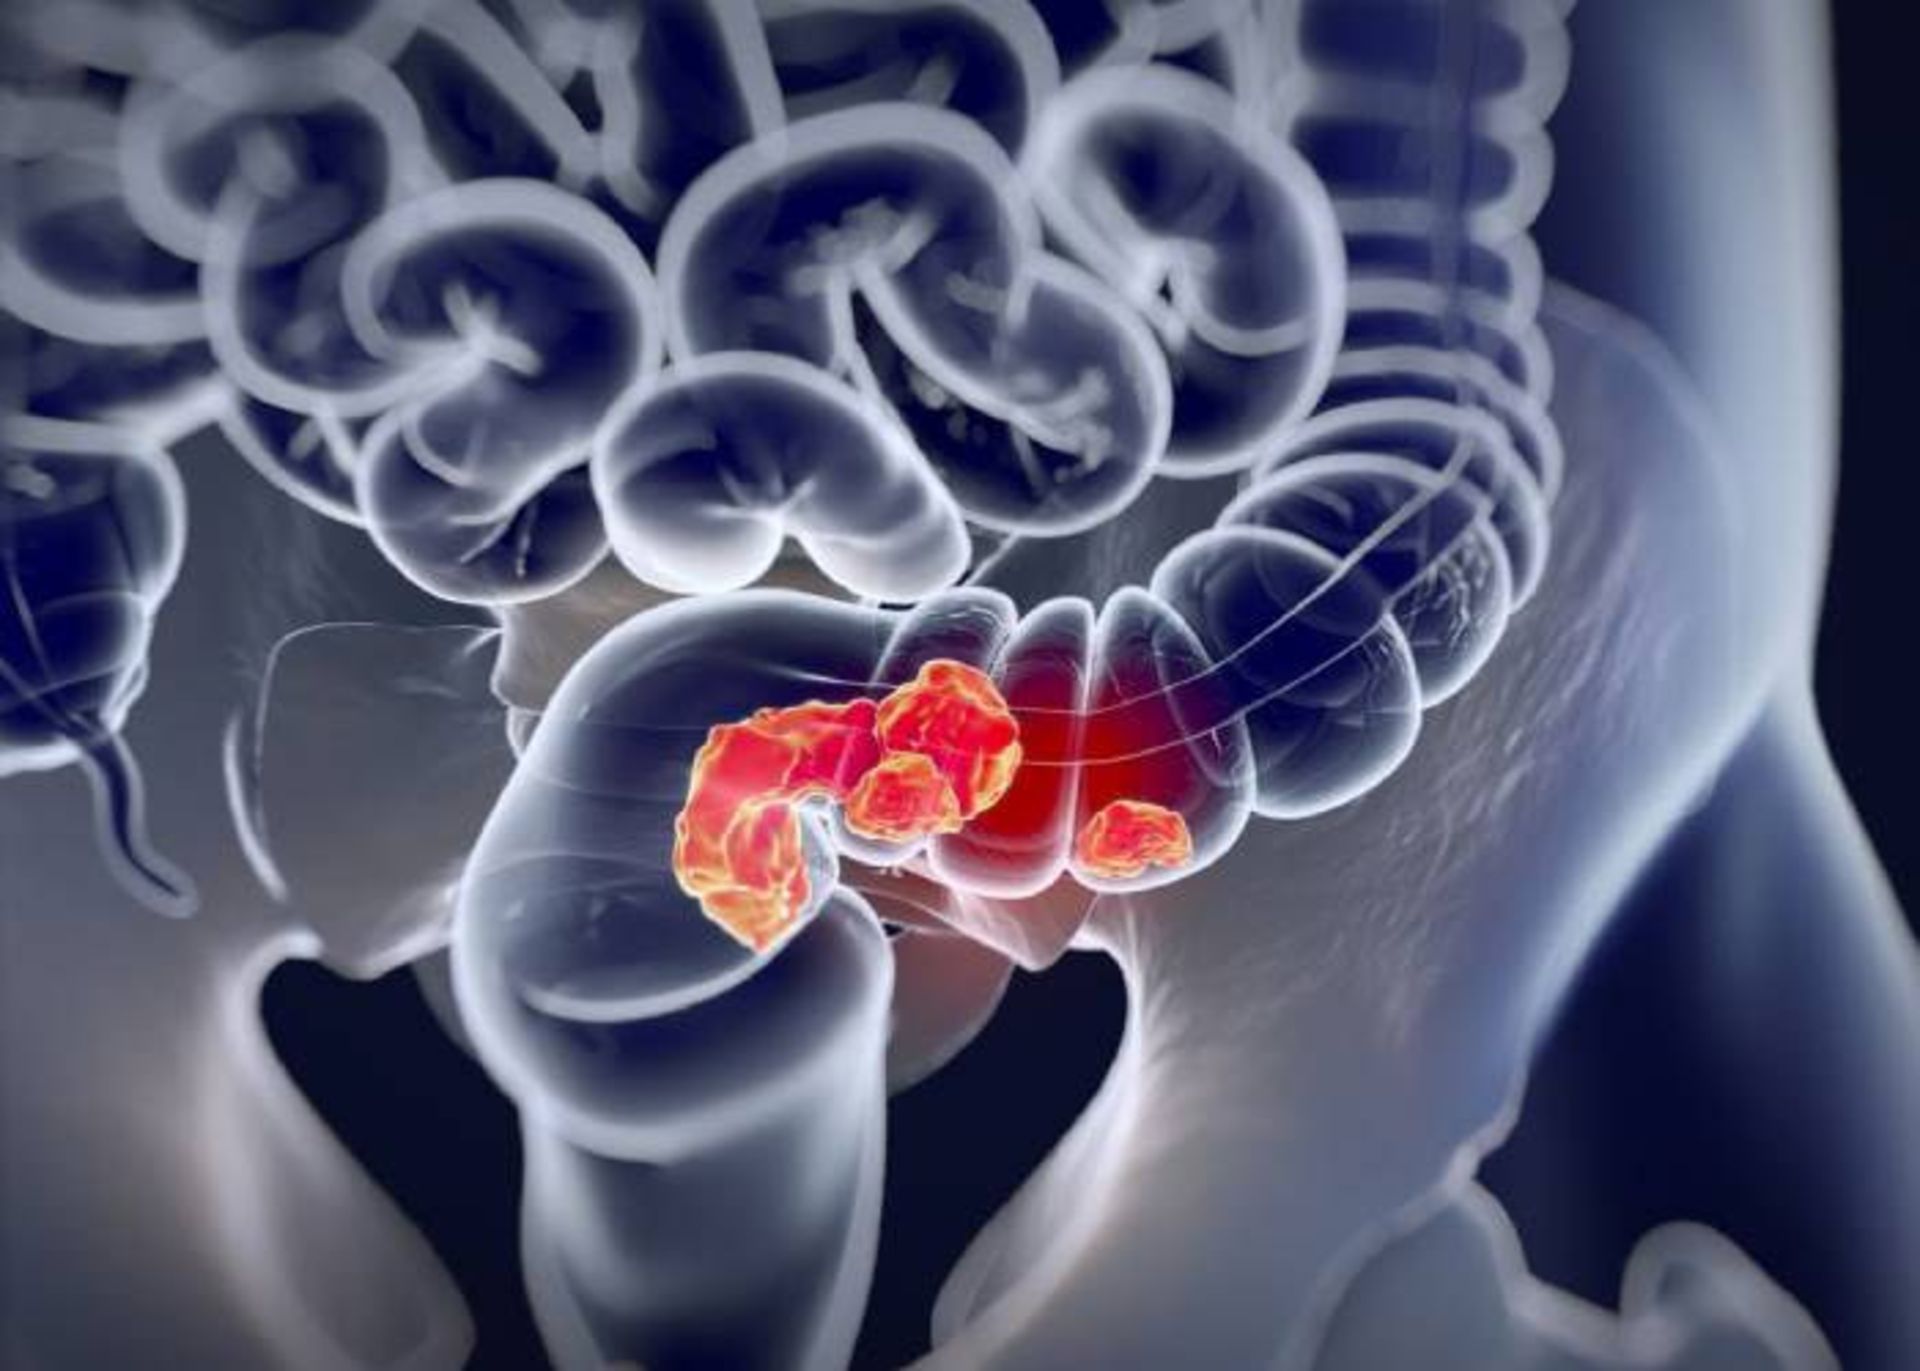

سرطان رودهی بزرگ دومین سرطان کشنده در جهان است که نهتنها تشخیص زودهنگام این نوع سرطان دشوار است؛ بلکه بسیاری از درمانهای فعلی تأثیرات محدودی بر بیماری میگذارند. تقریبا نیمی از افرادی که عمل رودهبرداری میشوند، بهعلت عود سرطان زنده نمیمانند. اکنون واکسن جدیدی برای تحریک سیستم ایمنی بیمار برای حمله و تخریب این نوع سرطان طراحی شده است.

موفقیت بزرگی که الهامبخش طراحی این واکسن خاص بود، کشف این موضوع بود که تقریبا در تمام سرطانهای رودهی بزرگ، ملکولی بهنام GUCY2C بیان میشود. اگرچه بهطورطبیعی این ملکول خاص در سلولهای سالم اپیتلیال روده نیز یافت میشود و بههمیندلیل، هر واکسنی که آنها را هدف قرار میدهد، باید سیستم ایمنی را فقط بهسمت تومورها و نه بافتهای سالم روده هدایت کند. هدف از این مرحله از آزمایش، ایجاد پروفایل ایمنی برای این واکسن بود.